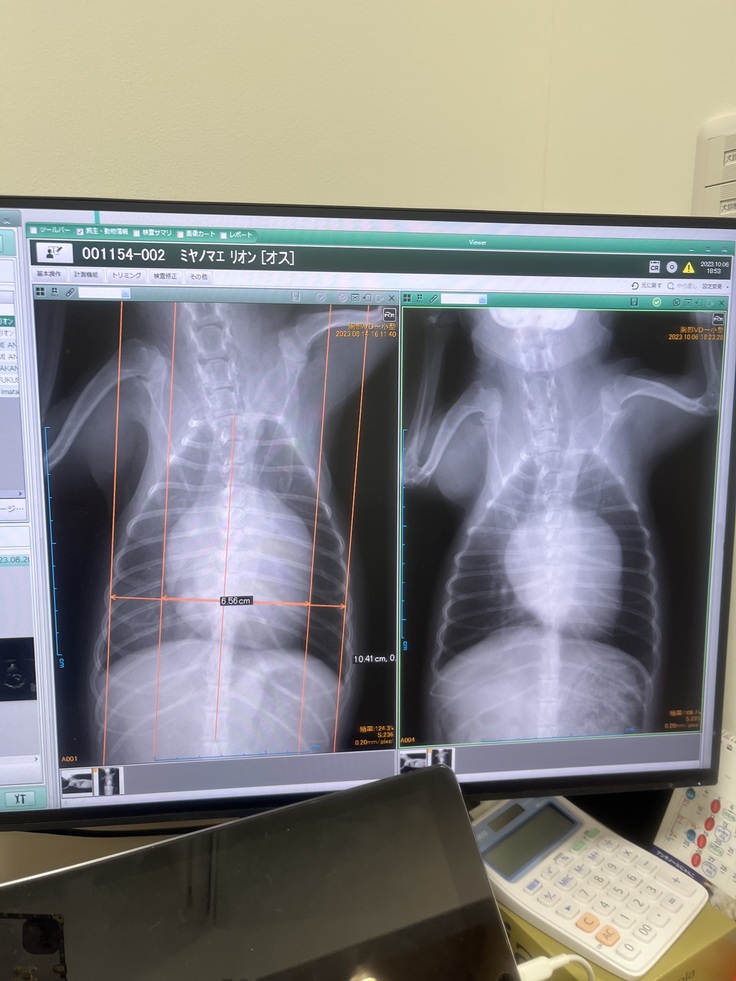

手術前の最後の検診

左が8/14 右が10/6

少し心臓が小さくなりました😌✨